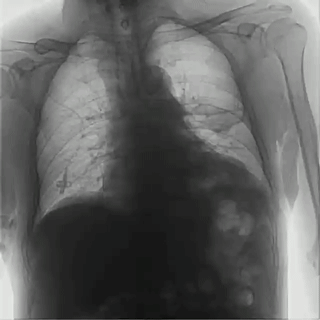

04百微平板,高清成像

普利德多功能動態(tài)DR采用100μm動態(tài)平板探測器,實(shí)現(xiàn)5.0lp/mm超高分辨率成像,大幅提升細(xì)節(jié)檢測能力;動態(tài)檢查幀率高達(dá)30幀/秒,有效避免漏診、誤診;靜態(tài)攝影有效像素高達(dá)1800萬,較之于傳統(tǒng)900萬點(diǎn)片像素,圖像細(xì)節(jié)更加清晰細(xì)膩,有助于醫(yī)生準(zhǔn)確判斷病灶的位置、形態(tài)和大小,為急診救治提供可靠依據(jù)。